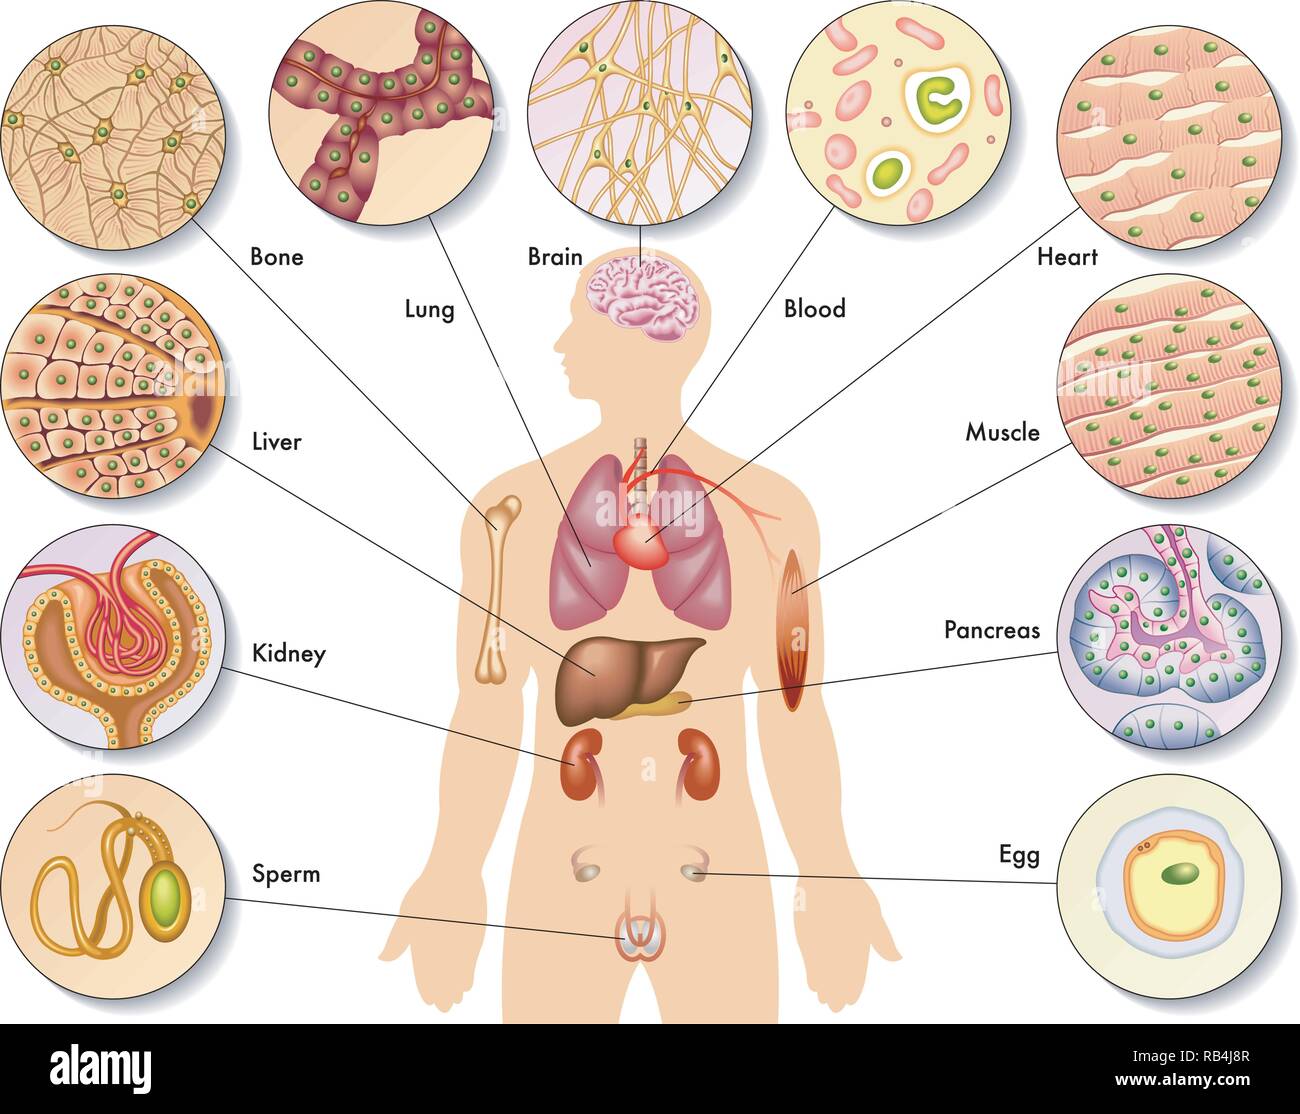

Medical illustration of the human body cells Stock Vectorhttps://www.alamy.com/image-license-details/?v=1https://www.alamy.com/medical-illustration-of-the-human-body-cells-image230598167.html

Medical illustration of the human body cells Stock Vectorhttps://www.alamy.com/image-license-details/?v=1https://www.alamy.com/medical-illustration-of-the-human-body-cells-image230598167.htmlRFRB4J8R–Medical illustration of the human body cells